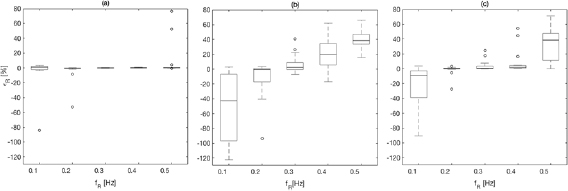

Results are shown in table 2, figures 4 and 5 for fPPG (a), CvPDR (b), and CvPDR+TR (c). Comparison of the methods shows different behaviors for different ranges:

- (i)The best results are obtained if the BR is in the range of

![$[0.2{{\rm \mbox{--}}}0.4]$](/img/lazy-loading-placeholder.gif) Hz. The median and interquartile ranges (IQRs) of

Hz. The median and interquartile ranges (IQRs) of  are below

are below  for fPPG and CvPDR+TR, but are higher for CvPDR. In particular, for the fPPG there is only one estimation with a relative error higher than

for fPPG and CvPDR+TR, but are higher for CvPDR. In particular, for the fPPG there is only one estimation with a relative error higher than  (defined as

(defined as  ) among all records within this range (0.2–0.4 Hz) for all subjects. For CvPDR,

) among all records within this range (0.2–0.4 Hz) for all subjects. For CvPDR,  corresponds to 43.1% of the estimations (13 at f R = 0.4 Hz) while for CvPDR+TR

corresponds to 43.1% of the estimations (13 at f R = 0.4 Hz) while for CvPDR+TR  (11.7%).

(11.7%). - (ii)In the boundary of the respiratory frequency range (f R = 0.1 Hz to f R = 0.5 Hz) there is a drastic drop in performances of vPPG-based systems compared to the fPPG system. At f R = 0.1 Hz, the decreased accuracy has a methodological reason. According to the developed method, the initialization should enlarge the respiratory frequency range to

![$[0.08{{\rm \mbox{--}}}0.5]$](/img/lazy-loading-placeholder.gif) Hz. However this condition is not always satisfied, leading to an overestimation of f R.

Hz. However this condition is not always satisfied, leading to an overestimation of f R.

Figure 4. Boxplot of the respiratory rate relative error, calculated for dataset I, obtained with fPPG (a), CvPDR (b), and CvPDR+TR (c).

Standard image High-resolution imageFigure 5. Bland–Altman plots for fPPG (a), CvPDR (b), and CvPDR+TR (c).

Standard image High-resolution imageTable 2. Relative error  in database I, expressed as median and interquartile ranges (IQRs).

in database I, expressed as median and interquartile ranges (IQRs).

| f R (Hz) | fPPG | CvPDR | CvPDR+TR | ||||||

|---|---|---|---|---|---|---|---|---|---|

(%) (%) |

IQR (%) |  |

(%) (%) |

IQR (%) |  |

(%) (%) |

IQR (%) |  |

|

| 0.1 | 0.89 | 4.56 | 1 | −37.78 | 89.30 | 11 | −8.80 | 35.69 | 6 |

| 0.2 | −0.59 | 0.75 | 1 | −0.56 | 17.70 | 5 | 0.26 | 1.11 | 1 |

| 0.3 | −0.14 | 0.51 | 0 | 2.43 | 9.41 | 4 | 0.49 | 3.62 | 2 |

| 0.4 | 0.12 | 0.63 | 0 | 19.93 | 28.82 | 13 | 1.94 | 3.88 | 3 |

| 0.5 | 0.28 | 0.47 | 2 | 38.73 | 13.23 | 17 | 38.65 | 36.55 | 13 |

Note the increase in performance in all respiratory frequencies for CvPDR when the  signal is taken into account. The large benefits of using the

signal is taken into account. The large benefits of using the  signal are shown for f R = 0.2 and mainly f R = 0.4 Hz, where the median/IQR is clearly reduced.

signal are shown for f R = 0.2 and mainly f R = 0.4 Hz, where the median/IQR is clearly reduced.

Bland–Altman plots show a positive bias in all considered methods, indicating an underestimation of the respiratory rate. However, a detailed analysis of figure 5 indicates an overestimation at low respiratory rates. Additionally, fPPG presents a lower standard deviation (SD) than vPPG-based methods, and the inclusion of the tracking signal reduces the SD of the error.